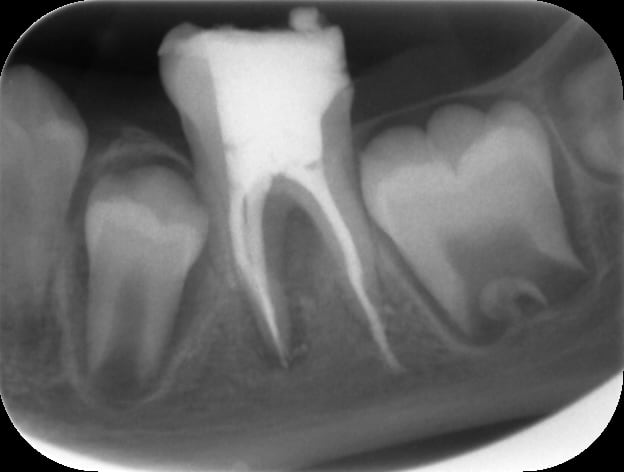

Je fais donc le parage: sous digue, avec hypochlorite , système de préparation Hero Shaper, radio cône calibré en place ok.

J'obture au Mac Spadden et je fais la radio post op: dépassement sur le canal distal, jusqu'au nerf alvéolaire inf !

Voici des radios:

Pre op tkcn8m - Eugenol